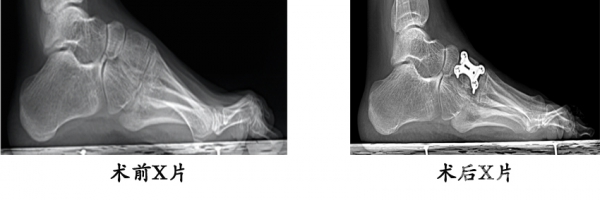

7.14岁女性,腓骨肌萎缩症,高弓足畸形。行内侧楔骨截骨、肌腱转位术,矫正畸形,恢复正常足弓。